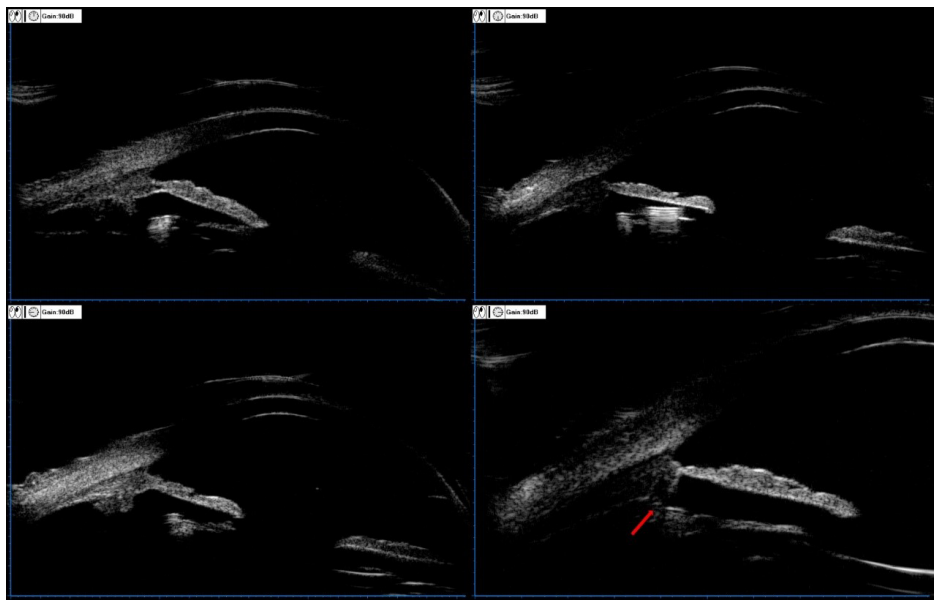

20230221164036_3661.png

图 2 左眼术前超声生物显微镜 (UBM) 图像

Figure 2 The preoperative UBM image of left eye

左眼中央前房深度 3.60 mm,虹膜形态极度后凹陷和反向瞳孔阻滞。

The depth of the central anterior chamber of the left eye is 3.60mm, extreme concave iris, and reverse pupillary block.